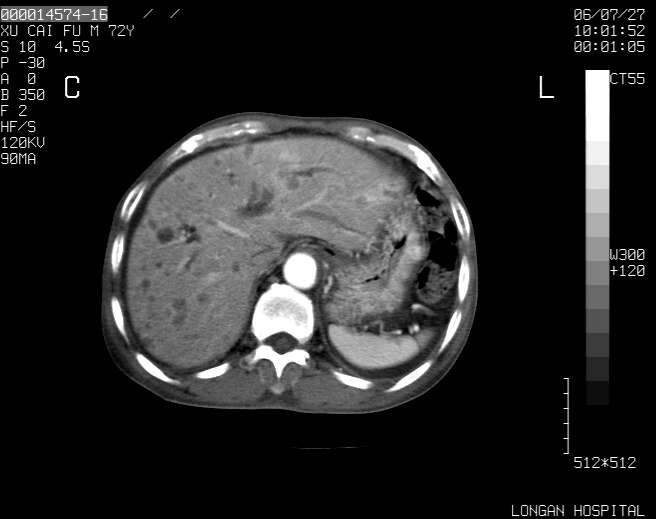

以下是引用winter在2006-7-30 20:14:00的发言:[br]1、考虑胆囊癌伴胆道侵犯并高位胆道梗阻、肝内多发转移、腹膜后淋巴结转移。[br]2、右肾轻度积水。[br]3、老人家72岁了胰腺头体尾部均较饱满,不过未见密度异常及其他异常征象。[br]4、腹水。

以下是引用jiajie在2006-7-31 7:10:00的发言:[br]考虑肝转移瘤,腹膜后淋巴结增大。[br]胃癌不能除外,建议胃镜检查。